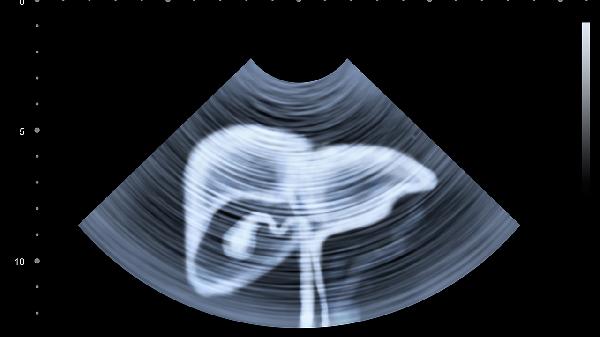

腹部胎兒最害怕母體接觸有害物質、感染、營養(yǎng)不良、缺氧以及強烈情緒波動等不良因素。這些因素可能影響胎兒正常發(fā)育,甚至導致流產、早產或先天缺陷。